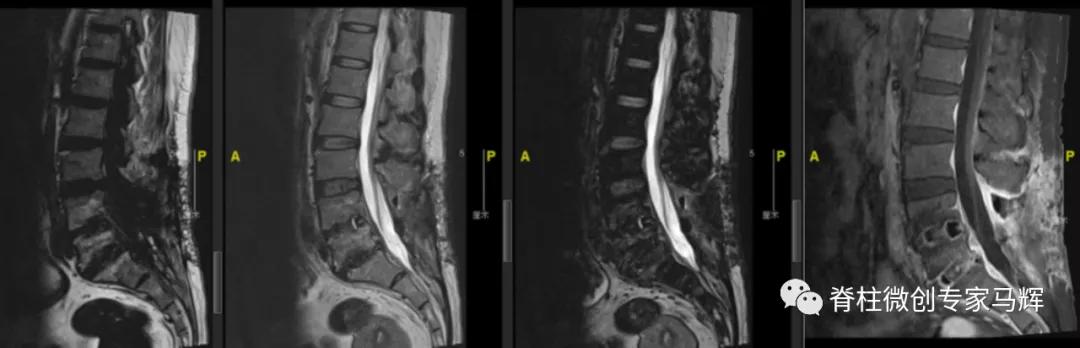

入院的时候,张女士有腰痛,左下肢疼痛无力伴发热6天,近3日疼痛加剧,翻身抬腿困难,发热最高达到38°C。根据症状,体格检查,实验室检查和影像检查,判断张女士可能存在脊髓硬膜外脓肿(SEA)压迫神经,以及感染的情况。为什么会出现这种状况呢?

对于无神经症状的SEA患者可采取单纯药物治疗。出现神经受压表现的患者需要采用外科减压术和抗生素治疗,以避免出现瘫痪的可能。经过讨论后,马辉主任团队决定对张女士进行脊柱后路脓肿清除加置管持续冲洗术,并进行血培养和脓液培养检查寻找可能的致病病原。

术中通过后外侧切口良好地显露了病灶范围,进行彻底的病灶清除,去除了压迫脊髓的脓肿,彻底清创之后进行一期闭合和加置管灌洗。术后患者腰痛及下肢疼痛马上消失,下肢活动自如,无明显麻木感。脓液培养提示金黄色葡萄球菌感染,予以敏感抗生素抗感染治疗。目前病情平稳,近期佩戴支具就可下地行走。